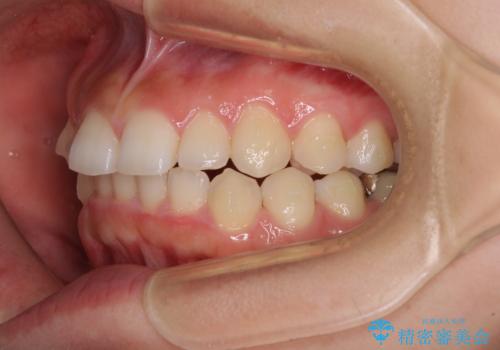

前歯のデコボコと突出感 インビザラインによる矯正治療

- 上下前歯のデコボコと、上顎前歯の突出感を気にして来院された患者様です。

インビザラインによる上下歯列の側方拡大と後方移動、IPR(歯と歯の間を削る)にるスペースの獲得により歯列を整えることとしました。

毎日22時間以上しっかりとマウスピースを装着していただいたので、スムーズに治療が進みました。歯と歯の間を削ることでうまくスペースコントロールでき、1年強で終えることができました。